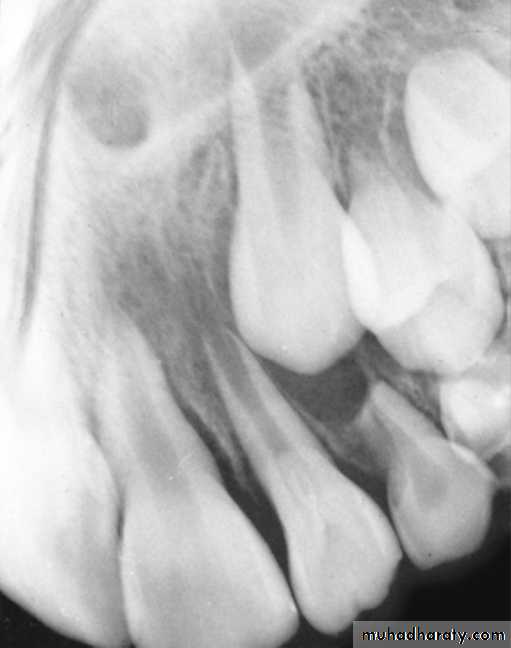

4. Dilacerated tooth

ReasonTrauma affecting the tooth bud during root formation